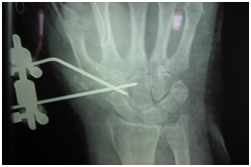

Evaluation of our primary results from the use of a mini ex-fix system for the treatment of the first carpometacarpal joint arthritis1-3 (Figure1).

Figure 1 Mini ex-fix system for the treatment of the first carpometacarpal joint arthritis.